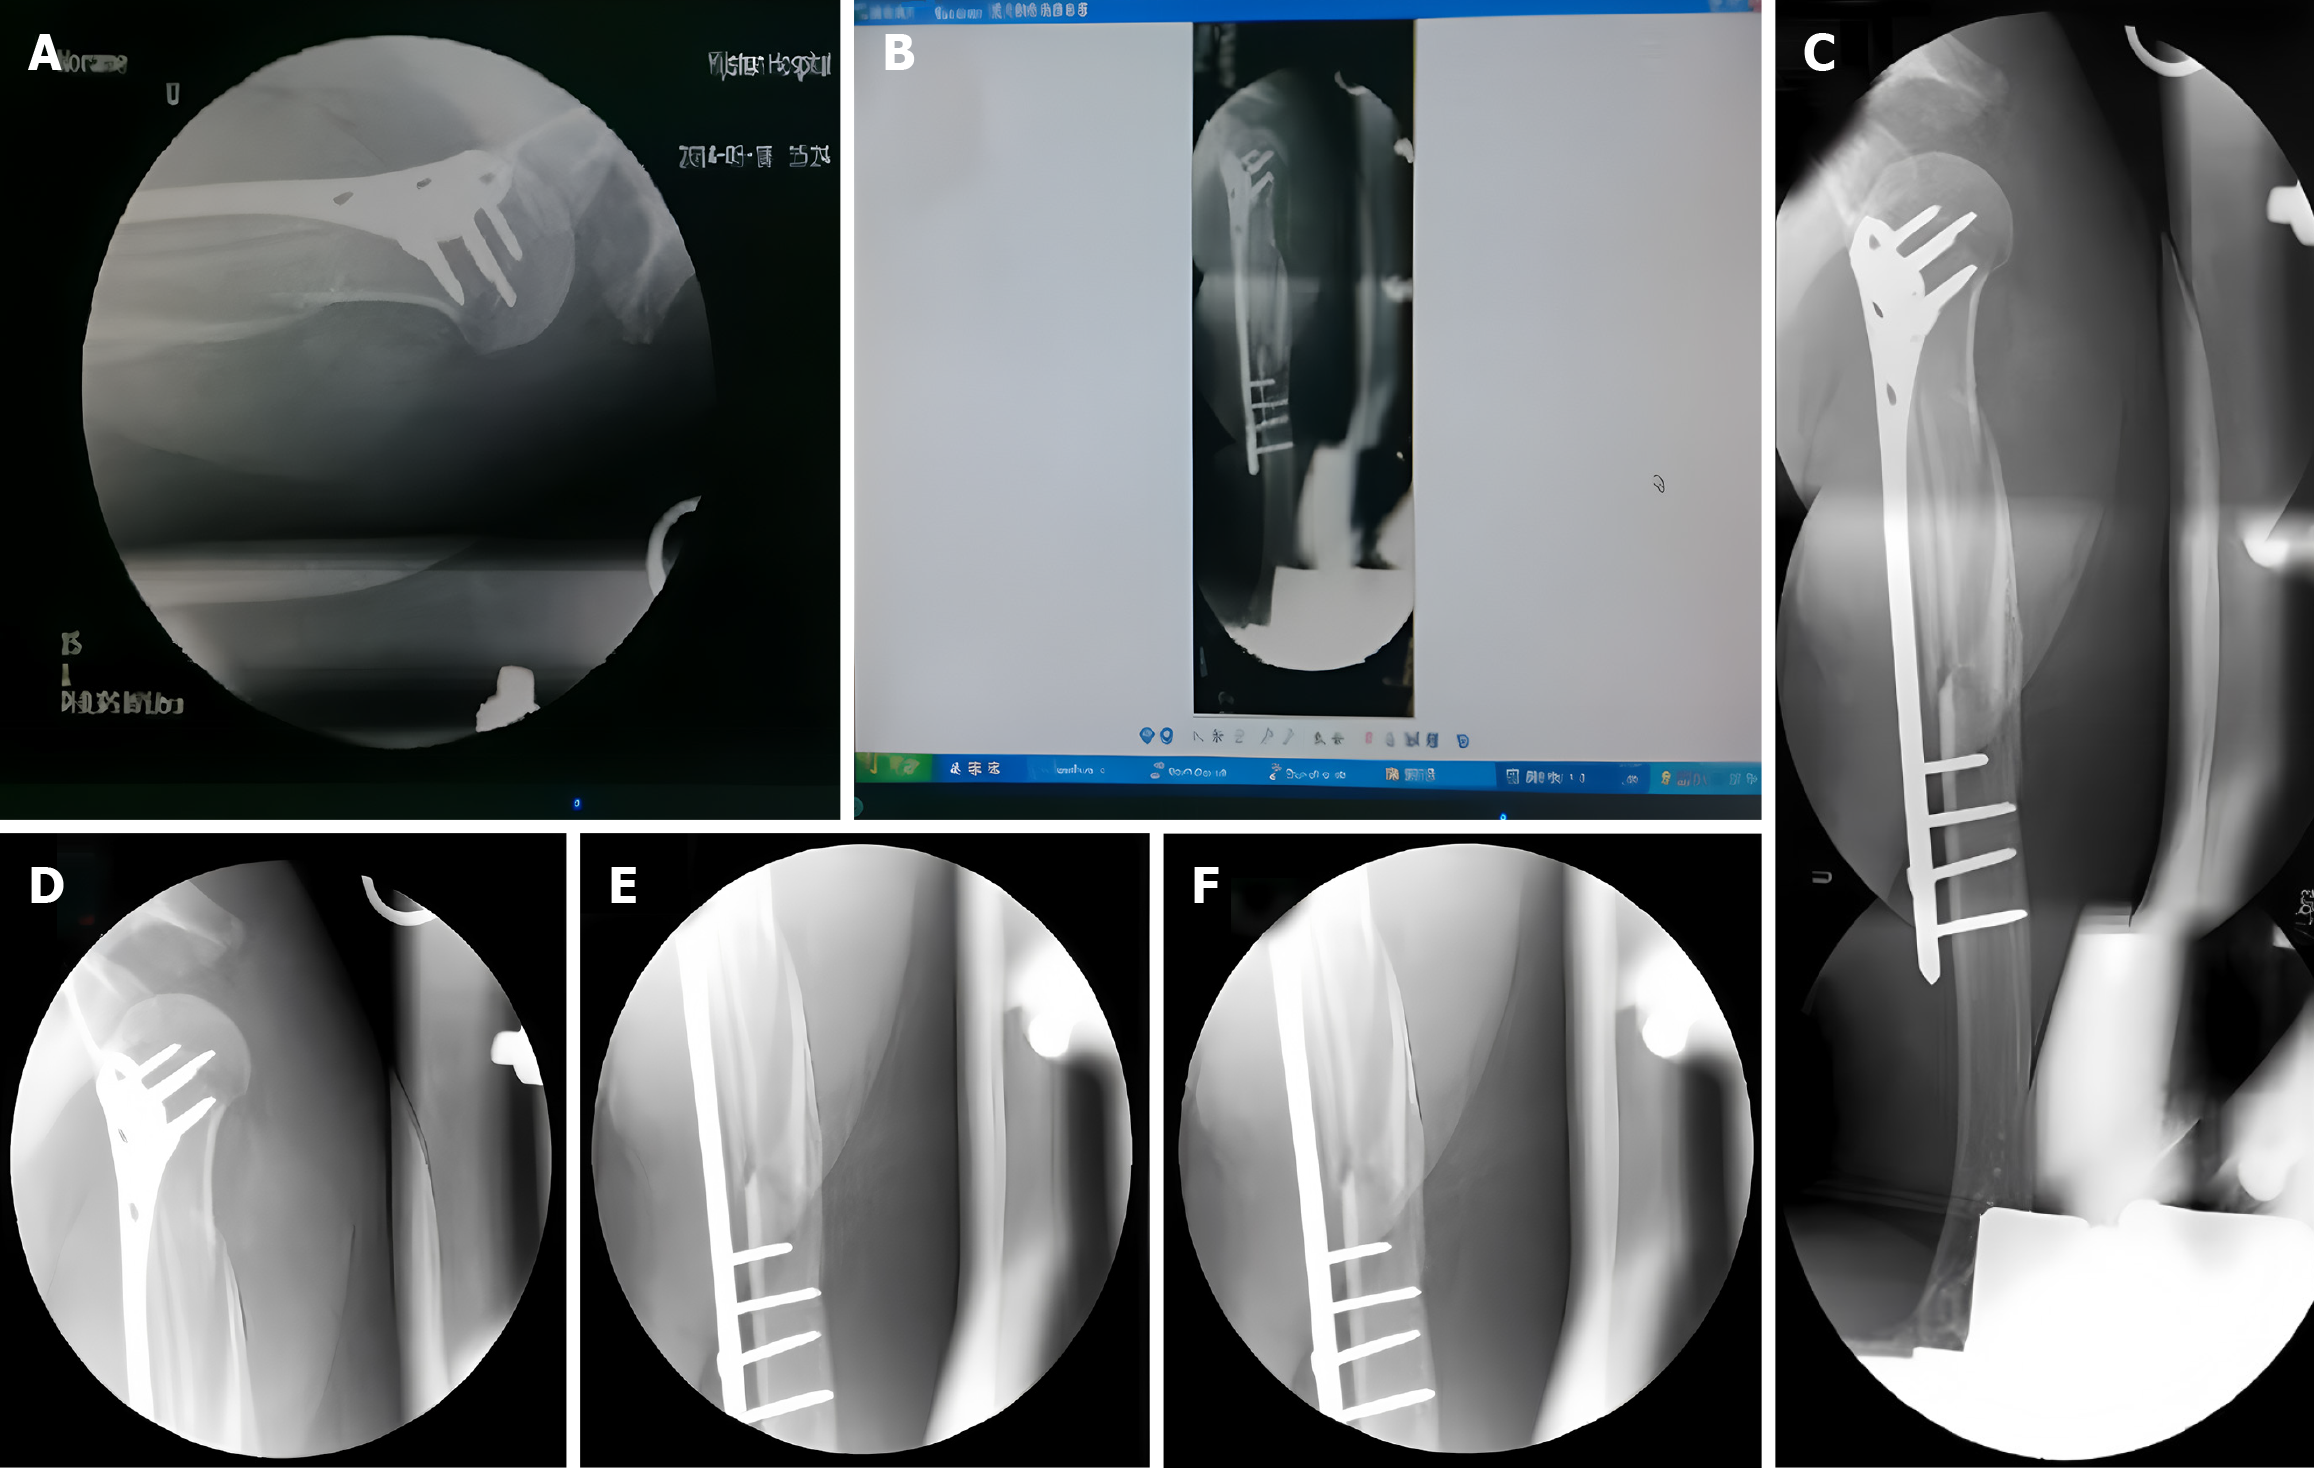

Figure 1 X-ray images.

A: The initial X-ray image taken by the C-arm; B: The professionally spliced X-ray film; C: The magnified X-ray film; D: C-arm fluoroscopy of the proximal humerus; E: C-arm fluoroscopy of the middle segment of the humerus; F: C-arm fluoroscopy of the distal humerus.